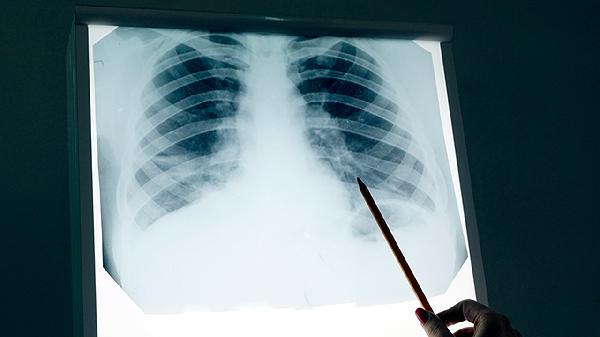

肺鳞癌晚期患者可以在医生指导下配合使用中药辅助控制病情,但无法替代手术、放疗或化疗等规范治疗。中药辅助治疗可能有助于缓解症状、改善生活质量,但具体效果因人而异。

部分中药成分可能通过调节免疫功能、抑制肿瘤血管生成或减轻放化疗副作用等方式发挥作用。临床常用的辅助中药包括黄芪注射液、康莱特注射液、华蟾素胶囊等,这些药物需在肿瘤科医生指导下使用。中药治疗肺鳞癌的临床研究数据有限,目前尚无明确证据表明单用中药可控制晚期肿瘤进展。部分患者使用中药后可能出现食欲改善、疼痛减轻等主观症状缓解,但需警惕虚假宣传或过度依赖中药延误规范治疗。

肺鳞癌晚期患者应优先考虑免疫治疗、靶向治疗等现代医学手段,中药可作为辅助疗法。建议选择正规中医院肿瘤科就诊,避免使用成分不明的偏方。治疗期间需定期复查肿瘤标志物和影像学检查,客观评估治疗效果。保持均衡饮食,适当补充优质蛋白和维生素,避免辛辣刺激性食物。根据体力状况进行温和运动如散步、太极拳等,维持心肺功能。家属应关注患者心理状态,必要时寻求专业心理支持。